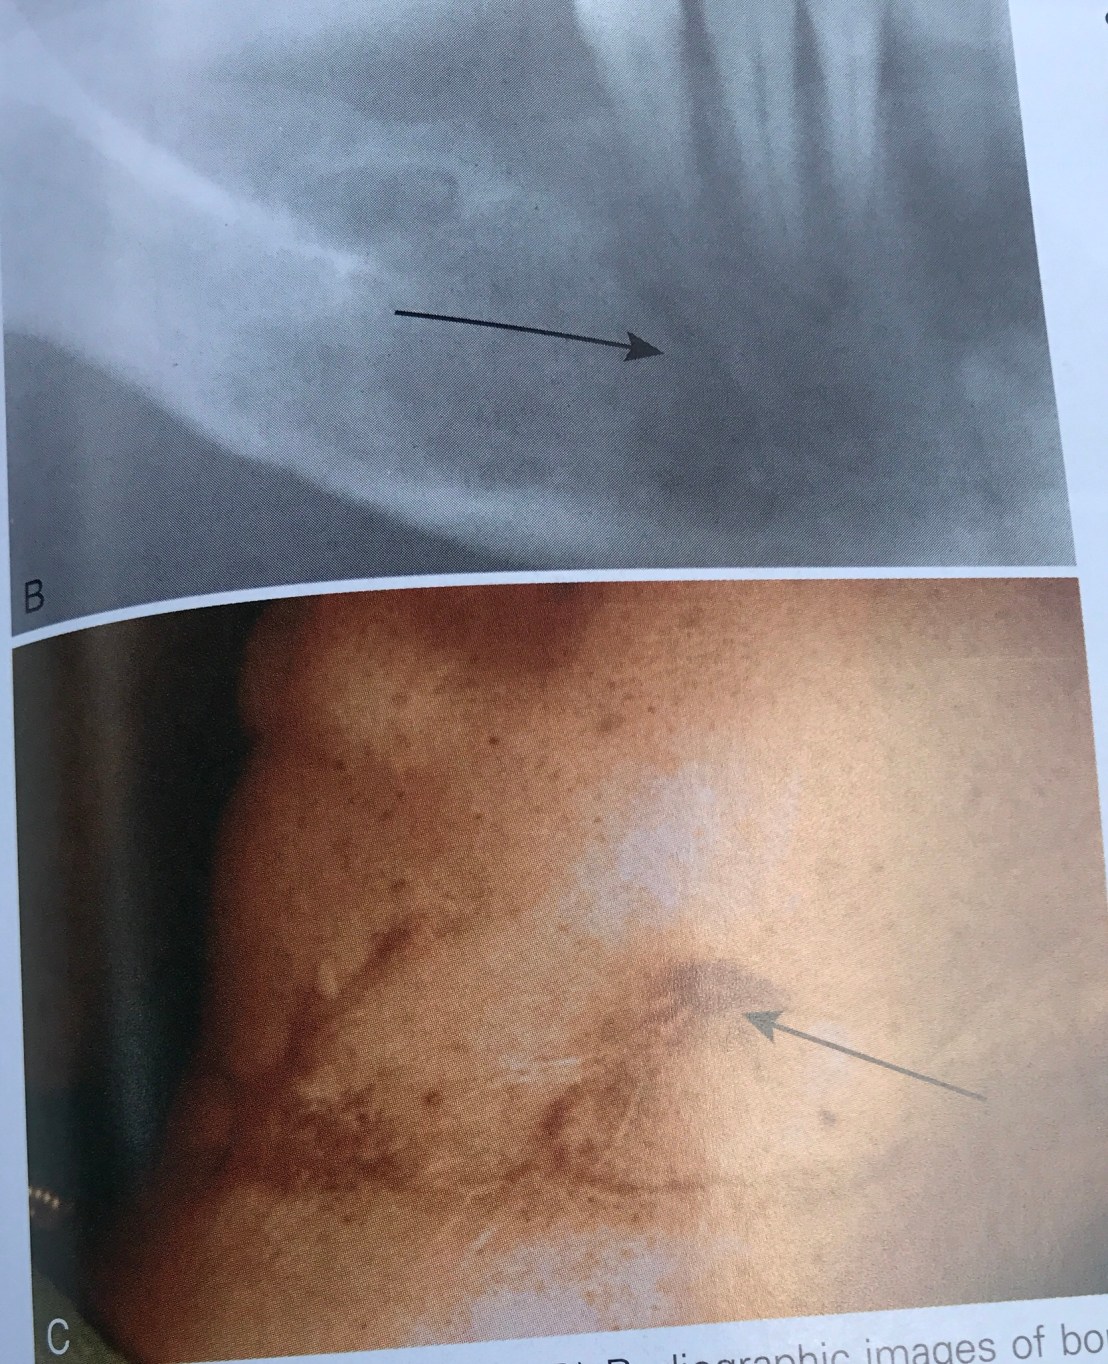

เคสนี้กลัว Graft ขยับครับ ใช้ screw ยาวจนทะลุ lingual cortical plate

ตำแหน่งที่ลูกศรชี้ในรูปแรกคือหาง screw ที่ทะลุด้าน lingual

ส่วนรูปร่าง แสดงการใช้ CBCT หาความยาว screw แบบความยาว ideal คือ ยึดจาก buccal cortical plate ถึง lingual cortical plate พอดี